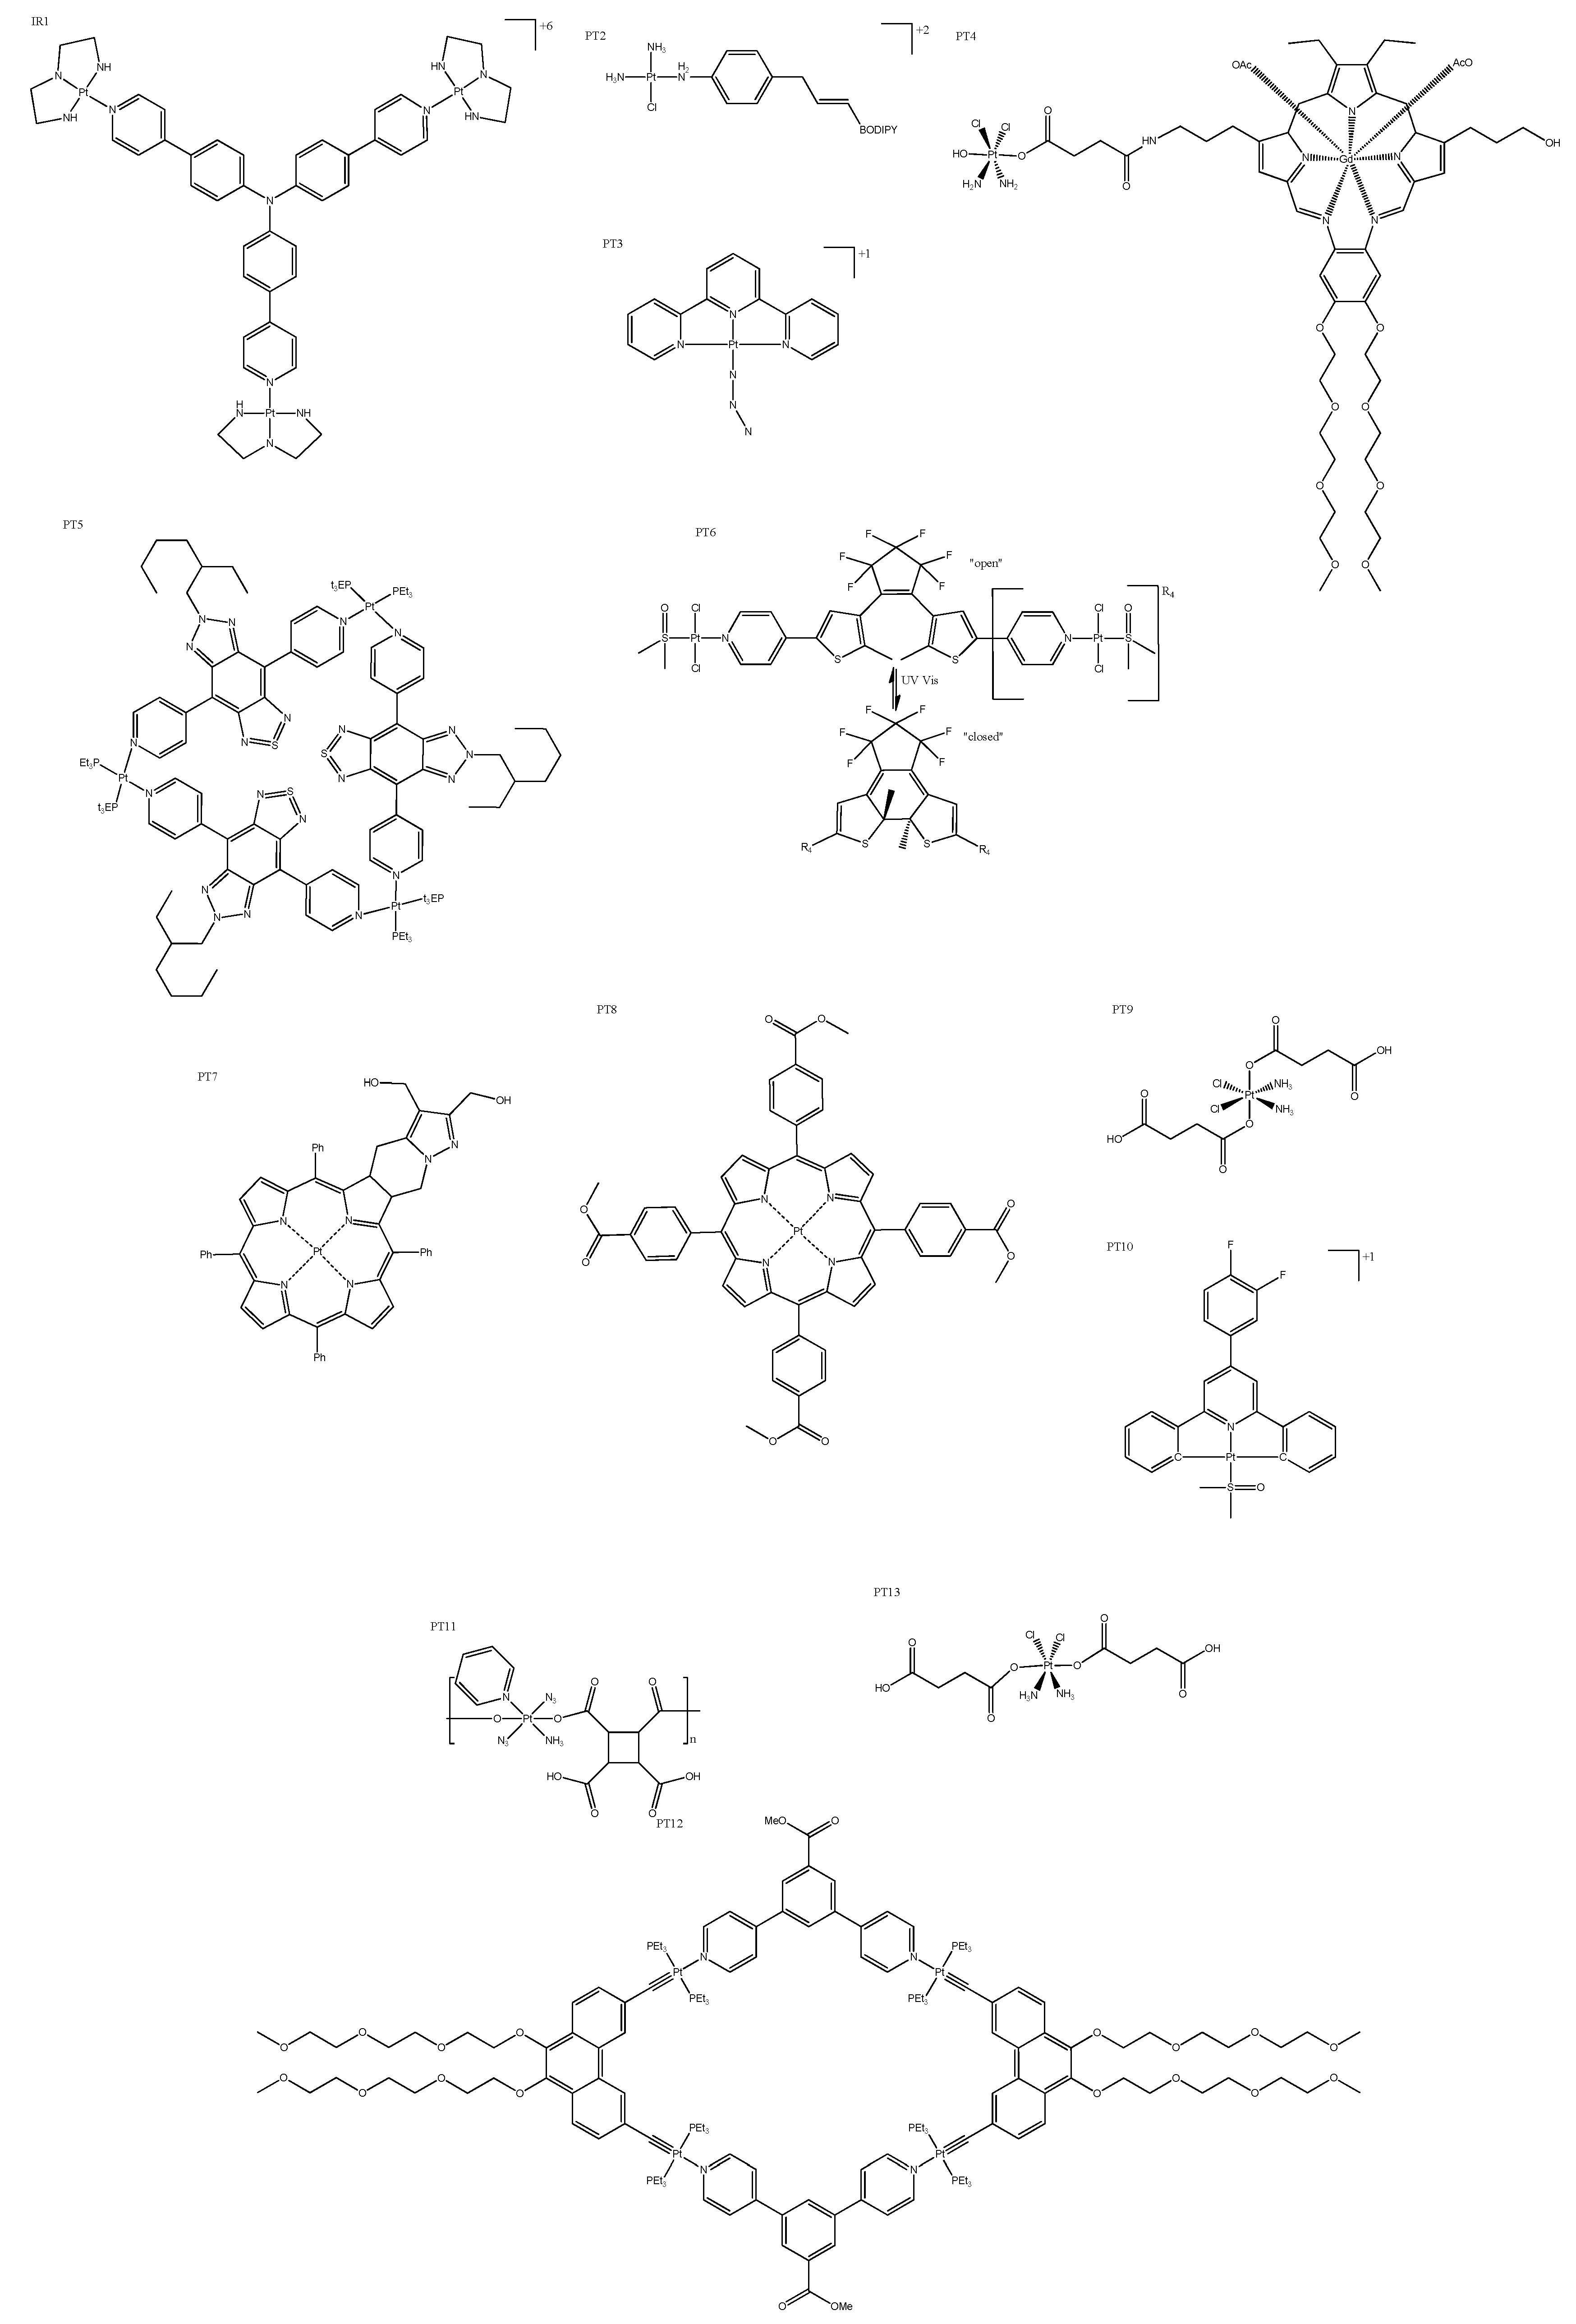

4. Platinum Complexes

4.1. Photosensitizers

4.2. Fluorescent Moiety

4.3. Cyclometallated Platinum Complexes

- Zhong, Y.-F.; Zhang, H.; Liu, W.-T.; Zheng, X.-H.; Zhou, Y.-W.; Cao, Q.; Shen, Y.; Zhao, Y.; Qin, P.Z.; Ji, L.-N.; et al. A Platinum(II)-Based Photosensitive Tripod as an Effective Photodynamic Anticancer Agent through DNA Damage. Chem. Eur. J. 2017, 23, 16442–16446. [Google Scholar] [CrossRef]

- Xue, X.; Zhu, C.; Chen, H.; Bai, Y.; Shi, X.; Jiao, Y.; Chen, Z.; Miao, Y.; He, W.; Guo, Z. A New Approach to Sensitize Antitumor Monofunctional Platinum(II) Complexes via Short Time Photo-Irradiation. Inorg. Chem. 2017, 56, 3754–3762. [Google Scholar] [CrossRef]

- Shi, H.; Clarkson, G.J.; Sadler, P.J. Dual Action Photosensitive Platinum(II) Anticancer Prodrugs with Photoreleasable Azide Ligands. Inorganica Chim. Acta 2019, 489, 230–235. [Google Scholar] [CrossRef]

- Thiabaud, G.; Arambula, J.F.; Siddik, Z.H.; Sessler, J.L. Photoinduced Reduction of PtIV within an Anti-Proliferative PtIV-Texaphyrin Conjugate. Chemistry 2014, 20, 8942–8947. [Google Scholar] [CrossRef] [Green Version]

- Lv, S.; Miao, Y.; Zheng, D.; Li, X.; Liu, D.; Song, F. Self-Assembled Platinum Supramolecular Metallacycles Based on a Novel TADF Photosensitizer for Efficient Cancer Photochemotherapy. Mol. Pharm. 2021, 18, 1229–1237. [Google Scholar] [CrossRef]

- Presa, A.; Vázquez, G.; Barrios, L.A.; Roubeau, O.; Korrodi-Gregório, L.; Pérez-Tomás, R.; Gamez, P. Photoactivation of the Cytotoxic Properties of Platinum(II) Complexes through Ligand Photoswitching. Inorg. Chem. 2018, 57, 4009–4022. [Google Scholar] [CrossRef] [PubMed] [Green Version]

- Laranjo, M.; Aguiar, M.C.; Pereira, N.A.M.; Brites, G.; Nascimento, B.F.O.; Brito, A.F.; Casalta-Lopes, J.; Gonçalves, A.C.; Sarmento-Ribeiro, A.B.; Pineiro, M.; et al. Platinum(II) Ring-Fused Chlorins as Efficient Theranostic Agents: Dyes for Tumor-Imaging and Photodynamic Therapy of Cancer. Eur. J. Med. Chem. 2020, 200, 112468. [Google Scholar] [CrossRef] [PubMed]

- Li, S.-Y.; Xie, B.-R.; Cheng, H.; Li, C.-X.; Zhang, M.-K.; Qiu, W.-X.; Liu, W.-L.; Wang, X.-S.; Zhang, X.-Z. A Biomimetic Theranostic O2-Meter for Cancer Targeted Photodynamic Therapy and Phosphorescence Imaging. Biomaterials 2018, 151, 1–12. [Google Scholar] [CrossRef] [PubMed]

- Xu, J.; Kuang, Y.; Lv, R.; Yang, P.; Li, C.; Bi, H.; Liu, B.; Yang, D.; Dai, Y.; Gai, S.; et al. Charge Convertibility and near Infrared Photon Co-Enhanced Cisplatin Chemotherapy Based on Upconversion Nanoplatform. Biomaterials 2017, 130, 42–55. [Google Scholar] [CrossRef]

- Zhang, Q.; Wang, S.; Zhu, Y.; Zhang, C.; Cao, H.; Ma, W.; Tian, X.; Wu, J.; Zhou, H.; Tian, Y. Functional Platinum(II) Complexes with Four-Photon Absorption Activity, Lysosome Specificity, and Precise Cancer Therapy. Inorg. Chem. 2021, 60, 2362–2371. [Google Scholar] [CrossRef]

- Kuang, G.; Lu, H.; He, S.; Xiong, H.; Yu, J.; Zhang, Q.; Huang, Y. Near-Infrared Light-Triggered Polyprodrug/SiRNA Loaded Upconversion Nanoparticles for Multi-Modality Imaging and Synergistic Cancer Therapy. Adv. Healthc. Mater. 2021, 10. [Google Scholar] [CrossRef]

- Sun, Y.; Ding, F.; Chen, Z.; Zhang, R.; Li, C.; Xu, Y.; Zhang, Y.; Ni, R.; Li, X.; Yang, G.; et al. Melanin-Dot-Mediated Delivery of Metallacycle for NIR-II/Photoacoustic Dual-Modal Imaging-Guided Chemo-Photothermal Synergistic Therapy. Proc. Natl. Acad. Sci. USA 2019, 116, 16729–16735. [Google Scholar] [CrossRef] [PubMed] [Green Version]

- Wang, H.; Lv, B.; Tang, Z.; Zhang, M.; Ge, W.; Liu, Y.; He, X.; Zhao, K.; Zheng, X.; He, M.; et al. Scintillator-Based Nanohybrids with Sacrificial Electron Prodrug for Enhanced X-Ray-Induced Photodynamic Therapy. Nano Lett. 2018, 18, 5768–5774. [Google Scholar] [CrossRef] [PubMed]

- Şahin, Ö.; Özdemir, Ü.Ö.; Seferoğlu, N.; Genc, Z.K.; Kaya, K.; Aydıner, B.; Tekin, S.; Seferoğlu, Z. New Platinum (II) and Palladium (II) Complexes of Coumarin-Thiazole Schiff Base with a Fluorescent Chemosensor Properties: Synthesis, Spectroscopic Characterization, X-ray Structure Determination, in vitro Anticancer Activity on Various Human Carcinoma Cell Lines and Computational Studies. J. Photochem. Photobiol. B 2018, 178, 428–439. [Google Scholar] [CrossRef] [PubMed]

- Schlagintweit, J.F.; Jakob, C.H.G.; Meighen-Berger, K.; Gronauer, T.F.; Weigert Muñoz, A.; Weiß, V.; Feige, M.J.; Sieber, S.A.; Correia, J.D.G.; Kühn, F.E. Fluorescent Palladium(II) and Platinum(II) NHC/1,2,3-Triazole Complexes: Antiproliferative Activity and Selectivity against Cancer Cells. Dalton Trans. 2021, 50, 2158–2166. [Google Scholar] [CrossRef]

- Hadian Rasanani, S.; Eslami Moghadam, M.; Soleimani, E.; Divsalar, A.; Ajloo, D.; Tarlani, A.; Amiri, M. Anticancer Activity of New Imidazole Derivative of 1R,2R-Diaminocyclohexane Palladium, and Platinum Complexes as DNA Fluorescent Probes. J. Biomol. Struct. Dyn. 2018, 36, 3058–3076. [Google Scholar] [CrossRef]

- Lo, A.T.S.; Bryce, N.S.; Klein, A.V.; Todd, M.H.; Hambley, T.W. Novel Polyamide Amidine Anthraquinone Platinum(II) Complexes: Cytotoxicity, Cellular Accumulation, and Fluorescence Distributions in 2D and 3D Cell Culture Models. J. Biol. Inorg. Chem. 2021, 26, 217–233. [Google Scholar] [CrossRef]

- Millán, G.; Giménez, N.; Lara, R.; Berenguer, J.R.; Moreno, M.T.; Lalinde, E.; Alfaro-Arnedo, E.; López, I.P.; Piñeiro-Hermida, S.; Pichel, J.G. Luminescent Cycloplatinated Complexes with Biologically Relevant Phosphine Ligands: Optical and Cytotoxic Properties. Inorg. Chem. 2019, 58, 1657–1673. [Google Scholar] [CrossRef]

- Lázaro, A.; Balcells, C.; Quirante, J.; Badia, J.; Baldomà, L.; Ward, J.S.; Rissanen, K.; Font-Bardia, M.; Rodríguez, L.; Crespo, M.; et al. Luminescent PtII and PtIV Platinacycles with Anticancer Activity Against Multiplatinum-Resistant Metastatic CRC and CRPC Cell Models. Chemistry 2020, 26, 1947–1952. [Google Scholar] [CrossRef]

| Pt Complex | IC50 (μM) | Luminescence | Special Features | ||

|---|---|---|---|---|---|

| Dark (Cell Line) | Light (Irradiation nm) | λEm(max) (nm) | λEx(max) (nm) | ||

| PT2 | >50 (HeLa) | 7.4 ± 0.3(635) | 550–650 | 566 | Positively charged Pt(II) center not only provided the cell membrane with an anchoring ability, but also made the complex a mild photosensitizer. |

| PT6 | >75 (A375) | 3.1 ± 0.2(365) | 470 | 300 | Light-mediated conversion from open to closed. |

| PT9 | None (HeLa) | “Increased” (NIR) * | Negatively charged in normal physiological conditions, and converted to positive charge in acidic tumor extracellular microenvironments. | ||

| PT15 | 410, 470 | 300 | DNA groove via hydrogenic or hydrophobic interaction. | ||

| PT16 | 16.2 ± 0.3 (MDA-MB-231) | 615 | 525 | Spheroid penetration. | |

| PT17a | 20.29 ± 2.10 (HeLa) | 400 | 475 | Shows potential as an anti-tubulin agent, and also provides useful information for our understanding of the mechanism responsible for the cytotoxic activity caused by these cyclometallated complexes. | |

| PT17b | 12.45 ± 2.50 (HeLa) | 388 | 458 | Selective generation of oxidative stress in cancer cells over noncancerous cells. | |